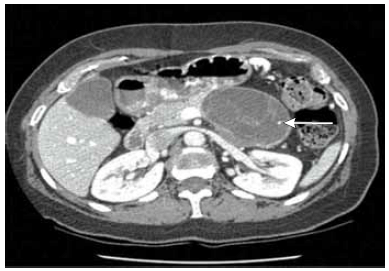

Mulher de 52 anos procura atendimento médico com queixa de dor abdominal há 10 meses, de fraca intensidade, sem relação com alimentação e ausência de alteração do hábito intestinal. Na investigação de seu quadro, solicitou-se tomografia abdominal, demonstrada a seguir (lesão apontada pela seta). Realizada punção aspirativa com agulha fina, cujo resultado demonstrou aspirado rico em mucina, níveis elevados de CEA e estroma similar ao do ovário.

O diagnóstico é de